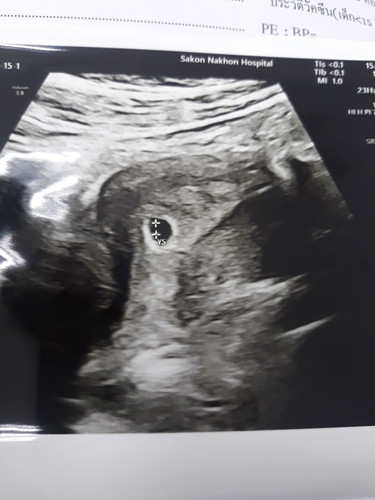

ช่วยดูผลอัลตร้าซาวหน่อยค่ะ

ท้อง5วีคหมอบอกถุงตั้งครรภ์เล็กบอกแค่นี้แล้วไม่ได้บอกอะไรต่อสรุปมีตัวออ่นยังค่ะช่วยดูหน่อยค่ะคือท้องแรกไม่ค่อยเข้าใจค่ะ

ซาวด์ทางหน้าท้องหรือช่องคลอดคะแม่ ถ้าทางหน้าท้อง ถ้าตัวอ่อนยังเล็กมากๆ หรือเป็นคนหน้าท้องหนา อาจจะยังไม่เห็นค่ะแม่ ทางช่องคลอดจะพอมีลุ้นมากกว่าค่ะ ทั้งนี้เป็นไปได้ว่า อายุครรภ์อาจจะน้อยกว่าที่นับ เพราะไข่อาจจะตกช้ากว่ากำหนด ตัวอ่อนยังเล็กมากอยู่ จึงยังไม่พบ ก็เป็นได้ค่ะแม่ ทานโฟลิคทุกวัน พักผ่อนเยอะๆ นะคะ ซาวด์ครั้งหน้าอาจจะได้เจอกันแล้วจ๊ะ

Đọc thêmยังไม่เห็นนะคะรออีกหน่อยนึงแม่ ยังท้องอ่อนมากๆ